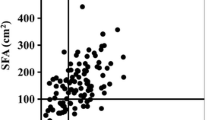

Figure 2 shows the positive correlation between the VFA level and the HOMA index values (r = 0.569, p < 0.0001; Fig. 2a) and the negative correlation between the VFA level and the H/M ratios measured using cardiac 123I-MIBG scintigraphy during the delayed phase (r = −0.509, p = 0.0005; Fig. 2b) in type 2 diabetes mellitus.

Multiple regression analysis was performed using the stepwise procedure. The level of VFA was predicted from the HOMA index values and the H/M ratio during the delayed phase (Table 4). In the other model analysis, the H/M ratio during the delayed phase was independently predicted from the level of VFA and the HOMA index values (data not shown).